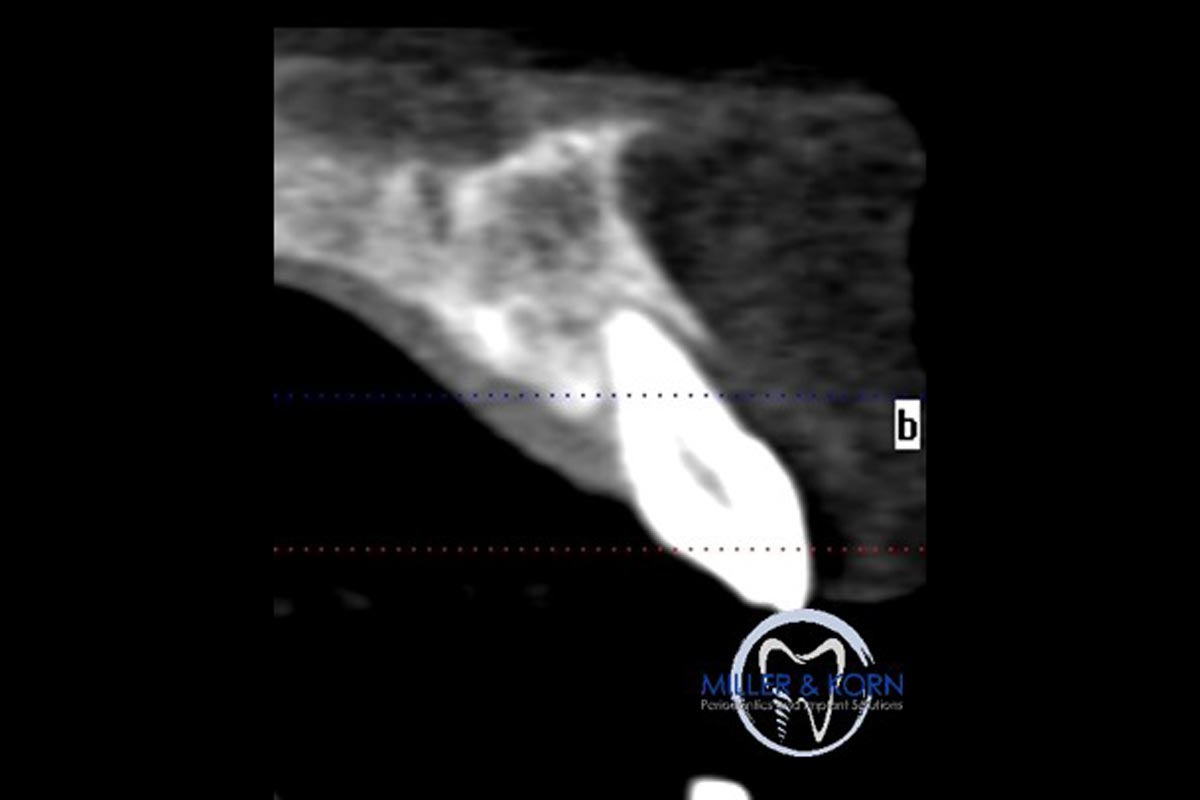

01/39 - The patient presented with pathologic mobility of upper left central incisor. Radiographic examination revealed significant circumferential attachment loss with an unfavorable crown to root ratio.Immediate implant placement and correction of horizontal and vertical bone loss using an allograft bone ring, cerabone® and Jason® membrane - Drs. Miller and Korn

The patient presented with pathologic mobility of upper left central incisor. Radiographic examination revealed significant circumferential attachment loss with an unfavorable crown to root ratio.